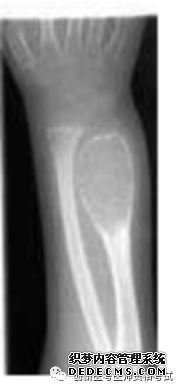

旋股内、外侧动脉的分支,是股骨头、颈的重要营养动脉。 股深动脉→旋股内侧动脉→骺外侧动脉供应股骨头2/3~4/5区域的血液循环,是股骨头最主要的供血来源。旋股内侧动脉损伤是导致股骨头缺血坏死的主要原因。 分类 1.按骨折线部位分类 (1)股骨头下骨折:易发股骨头缺血坏死。 (2)经股骨颈骨折:骨折线位于股骨颈中部,股骨头亦有明显供血不足,易发生股骨头缺血坏死,或骨折不愈合。 2.按骨折线方向分类 ①股骨颈外展骨折:Pauwel角<30°,骨折易愈合;②股骨颈内收骨折:Pauwel角>50° 外有小三,内人打我,婚姻不稳 临床表现 1.中、老年人有摔倒受伤史,伤后感髋部疼痛,下肢活动受限,不能站立和行走,应怀疑病人有股骨颈骨折。有时数天后发现。 2.患肢出现外旋畸形45°~60°之间。 若外旋畸形达到90°,应怀疑有转子间骨折。 3.可出现局部压痛及轴向叩击痛。 4.患肢短缩、大转子上移。在侧卧并半屈髋,由髂前上棘与坐骨结节之间画线,为Nelaton线(内拉东线),正常情况下,大转子在此线上,若大转子超过此线之上,表明大转子有向上移位。 治疗 1.非手术疗法 年龄过大,全身情况差,合并有严重心、肺、肾、肝等功能障碍不能耐受手术者,要尽早预防和治疗全身并发症,全身情况允许后尽早尽快手术治疗。可采用穿防旋鞋,下肢皮肤牵引,卧床6~8周。 2.手术治疗 股骨颈骨折以手术治疗为主 (1)闭合复位内固定术:是首选的手术方法。 (2)切开复位内固定术:适用于手法复位失败后固定不可靠,或青壮年陈旧骨折不愈合者。 (3)人工关节置换术:适用于全身情况尚好,GardenⅢ、Ⅳ型股骨颈骨折的老年患者。 表现:转子区出现疼痛,肿胀,瘀斑,下肢不能活动 查体:转子间压痛,下肢外旋畸形可达90°,有轴向叩击痛。下肢短缩。 治疗:稳定牵引 不稳定手术 临床表现 下1/3骨折 近端前上,远端向后。 有可能损伤腘动脉、腘静脉和胫神经、腓总神经 第二位容易休克的骨折(第一位为骨盆骨折)。 治疗 1.非手术疗法 (1)成人:麻醉下,在胫骨结节或股骨髁上进行骨骼牵引 持续牵引8~10周 (2)儿童:3岁以下儿童采用垂直悬吊皮肤牵引。 2.手术疗法 成人及三岁以上儿童股骨干骨折近年来多采用手术治疗。 (1)指征:①非手术疗法失败; ②同一肢体或其他部位有多处骨折; ③合并神经血管损伤; ④老年人的骨折,不宜长期卧床者; ⑤陈旧骨折不愈合或有功能障碍的畸形愈合; ⑥无污染或污染很轻的开放性骨折。 (2)手术治疗方法: ①切开复位,钢板螺钉内固定; ②带锁髓内钉内固定; ③弹性钉内固定; ④外固定架外固定。 治疗 必须坚持解剖复位、坚强固定,有骨缺损时应及时植骨填充。 1.胫骨干横切面呈三棱形,在中、下1/3交界处,变成四边形。 2.容易开放性骨折。 3.下1/3段骨折愈合较慢,容易发生延迟愈合或不愈合。 并发症 1.易发生创伤性关节炎。 2.胫骨上1/3骨折,可致胫后动脉损伤,引起下肢严重血循环障碍,甚至缺血坏死。 3.中1/3:骨筋膜室综合征 4.胫骨下1/3段骨折:骨不愈合。 5.腓骨骨折:腓总神经损伤,造成足下垂、趾背伸无力和足背外侧感觉障碍。 治疗 1.单纯胫骨干骨折采用手法复位,小夹板或石膏固定10~12周。 2.单纯腓骨干骨折,若不伴有关节分离,亦不需特殊治疗。可用石膏固定3~4周。 3.不稳定的胫腓骨干双骨折在以下情况时,采用切开复位内固定: ①手法复位失败; ②严重粉碎性骨折或双段骨折; ③污染不重,受伤时间较短的开放性骨折。 踝部骨折和踝部扭伤 踝关节是人体负重的主要关键 1.内侧副韧带 又称三角韧带,是踝关节最坚强的韧带。主要功能是防止踝关节外翻。 2.外侧副韧带 起自外踝,分三束分别止于距骨前外侧跟骨外侧和跟骨后方,是踝部最薄弱的韧带。 内人是坚强的后盾,防止外翻 外侧是最薄弱的韧带 1.压缩骨折:为最常见的脊柱骨折类型。 2.爆裂骨折:垂直型压缩性骨折,易截瘫 3.Chance骨折:为经椎体、椎弓及棘突的水平状撕裂性损伤,为不稳定性骨折,临床上比较少见。 4.Jefferson骨折:第一颈椎前、后弓双侧骨折 X线不易发现,CT清晰 影像学检查 1.X线正侧位摄片:是首选检查方法。 2.CT检查:可以显示出椎体的骨折情况 3.MRI检查:凡疑有脊髓、神经损伤 治疗 搬运:平托或整体滚动 脊柱手术指征: ①颈、胸、腰椎骨折脱位有关节突交锁; ②影像学检查有骨折碎片进入椎管内压迫脊髓; ③截瘫平面不断上升,提示有活动性出血者; ④手法复位不满意或存在脊柱不稳定。 骨盆骨折 1.常伴有严重多发伤,见有血压低、休克等。 2.骨盆骨折的主要体征: (1)骨盆分离试验与挤压试验阳性(题眼) (2)肢体长度不对称 (3)会阴部的瘀斑是耻骨和坐骨骨折的特有体征 常见并发症 1.腹膜后血肿 可以迅速致死。(不切开) 2.盆腔内脏损伤 诊断性腹腔穿刺吸出不凝血可考虑有内脏损伤。 3.膀胱与后尿道、直肠损伤损伤 血尿者考虑合并尿道、膀胱或肾的损伤。 4.脂肪栓塞与静脉栓塞 前脱位最多见 其他关节脱位均为后脱位多见 临床表现 1.方肩畸形:检查可发现患肩呈方肩畸形,肩胛盂处有空虚感,上肢有弹性固定。 2.Dugas征阳性:有脱位时将患侧肘部紧贴胸壁时,手掌搭不到健侧肩部,或手掌搭在健侧肩部时,肘部无法贴近胸壁,称Dugas征阳性。 治疗:手法复位 一般采用局部浸润麻醉,用足蹬法(Hippocrates法)复位。 复位后三角巾选吊周。 1.多发生在5岁以下的儿童 2.儿童的腕、手有被向上的牵拉受伤历史。 3.肘部疼痛受限 4.治疗 不用麻醉即可进行手法复位。 复位后不必固定。 1.后脱位最为常见。乘车跷二郎腿易发生 呈屈曲、内收、内旋畸形。(后内内) 大转子上移 2.前脱位典型表现 患肢呈屈曲、外展、外旋畸形。腹股沟处肿胀,可摸到股骨头。 治疗 复位宜早,最初24~48小时是复位的黄金时期 常用的复位方法Allis法(提拉法) 复位后用绷带将双踝暂时捆在一起 打篮球起跳损伤半月板,落地损伤前交叉。 走(轴移)厕(侧方应力)所拉(Lachman)抽(抽屉试验) 侧方应力为检查侧副韧带,其余均为检查交叉韧带。 1.侧方应力试验 在膝关节完全伸直位与屈曲30°位置下做被动膝内翻与膝外翻动作,并与对侧作比较。如有疼痛或发现内翻外翻角度超出正常范围并有弹跳感时,提示有侧副韧带扭伤或断裂。提示有侧副韧带扭伤或断裂。 2.抽屉试验 建议在麻醉下进行操作。膝关节屈曲90°,小腿垂下,检查者用双手握住胫骨上段做拉前和推后动作,并注意胫骨结节前后移动的幅度。 前移增加表示前交叉韧带断裂; 后移增加表示后交叉韧带断裂。 3.轴移试验 本试验用来检查前交叉韧带断裂后出现的膝关节不稳定。患者侧卧,检查者站在一侧,一手握住踝部,屈曲膝关节到90°,另一手在膝外侧施力,使膝处于外翻位置,然后缓慢伸直膝关节,至屈曲20°~30°位时觉疼痛与弹跳,是为阳性结果。提示前外侧旋转不稳定。 4.Lachiman试验 比抽屉试验阳性率高 MRI检查可以清晰地显示出前、后交叉韧带的情况。(首选) 半月板内侧程C 外侧O 检查方法:伸屈挤磨蹲 1.过伸试验 2.过屈试验 3.半月板旋转挤压试验 4.研磨试验 5.蹲走试验 首选MRI 半月板撕裂治疗:首选关节镜。 1.一般应争取在伤后6~8小时内进行。 2.手部创伤止血带缚于上臂上1/3处。 3.则应采用干燥冷藏法保存,即将断肢用无菌或清洁敷料包好,放入塑料袋中,再放在加盖的容器内,外周加冰块保存。但不能让断肢与冰块直接接触,以防冻伤,也不能用任何液体浸泡。 4.到达医院后,立即检查断肢,用无菌敷料包好,放在无菌盘上,置入4℃冰箱内。 5.若为多个手指,应分别予以标记 6.上臂和大腿离断,时限须严格控制,断指对全身影响小,则可延长至12~24小时。 断肢(指)再植的禁忌证 (1)患全身性慢性疾病,或合并严重脏器损伤,不允许长时间手术,或有出血倾向者。 (2)断肢(指)多发性骨折及严重软组织挫伤,血管床严重破坏,血管、神经、肌腱高位撕脱者。 (3)断肢(指)经刺激性液体及其他消毒液长时间浸泡者。 (4)在高温季节,离断时间过长,断肢未经冷藏保存者。 (5)病人精神不正常,本人无再植要求且不能合作者。 中(正中N)原(猿手)迟(尺N)早(爪形手)闹(桡N)炊烟(垂腕) 1.桡神经 垂腕”状态,各手指掌指关节不能背伸,拇指不能伸,前臂旋后障碍 手臂桡侧皮肤感觉减退或消失。感觉障碍以第1、2掌骨间隙背面“虎口区”皮肤最为明显。 2.尺神经损伤 肌肉:骨间肌、蚓状肌、拇收肌麻痹所致的第4、5指的指间关节弯曲,称为“爪形手”畸形 运动:手指内收(夹纸试验阳性)、外展障碍和Froment征 感觉:手部尺侧半和尺侧一个半手指感觉障碍。 3.正中神经损伤 前臂不能旋前,屈腕无力,拇、示指、中指不能屈曲,拇指不能对掌,鱼际肌萎缩,手掌平坦,称为“猿手”。 感觉障碍以拇指、示指和中指的末节为明显。亦可见明显的血管收缩和营养障碍。 1.坐骨神经损伤 髋关节后脱位、臀部刀伤、臀肌挛缩手术伤以及臀部肌注药物均可致其高位损伤 (1)股后部肌肉及小腿和足部所有肌肉全部瘫痪,导致膝关节不能屈、踝关节(屈伸)与足趾运动功能完全丧失,呈足下垂。 (2)小腿后外侧和足部感觉丧失,足部出现神经营养性改变。 2.腓总神经损伤 (1)腓总神经易在腘部及腓骨小头处损伤 (2)踝背伸、外翻功能障碍,呈内翻下垂畸形。以及伸踇、伸趾功能丧失,呈屈曲状态 1.本病有自限性,一般在6~24个月左右可自愈 2.发病年龄50岁左右,女性多于男性。左侧多于右侧3.肩周痛以肩袖间隙区、肱二头肌长腱压痛为主。 4.肩各方向主动、被动活动均不同程度受限。 5.X线片见肩关节结构正常。MRI见关节囊增厚,当厚度>4mm对诊断本病的特异性达95%。 治疗 1.早期给予理疗、针灸、适度的推拿按摩 2.痛点局限时,可局部注射醋酸泼尼松龙。 3.短期服用非甾体抗炎药 4.应每日进行肩关节的主动活动。 5.以上治疗无效时,在麻醉下采用手法或关节镜松解粘连,然后再注入类固醇或透明质酸钠,可取得满意疗效。 伸肌腱牵拉试验(Mills征):伸肘,握拳,屈腕,然后前臂旋前,此时肘外侧出现疼痛为阳性。有时疼痛可牵涉到前臂伸肌中上部。 治疗 1.限制用力握拳、伸腕:治疗和预防复发的关键。( 2.首选封闭,制动压痛点可采用局部药物行封闭治疗,只要注射准确,均能取得极佳的近期效果。疗效是否巩固,与能否适当限制腕关节活动关系很大。这是肱骨外上髁炎首选的治疗方法。 1.弹响指、弹响拇 2.各手指发病的频度依次为中、环指最多,示、拇指次之,小指最少。 3.疼痛常在近侧指间关节,而不在掌指关节。 4.体检时可在远侧掌横纹处扪及黄豆大小的痛性结节,屈伸患指该结节随屈肌腱上、下移动,或出现弹拨现象,并感到弹响即发生于此处。 5.儿童拇长屈肌腱鞘炎常为双侧 6.桡骨茎突狭窄性腱鞘炎:握拳尺偏腕关节时,桡骨茎突处出现疼痛,称Finkelstein试验阳性。 治疗 1.局部制动和局部封闭 2.非手术无效,腱鞘切开减压术 Dugas症. Froment症 Thomas症 Mills症 Finkelsein症 1.创伤性因素 2.非创伤性因素 ①长期应用激素;②乙醇中毒;③减压病;④镰状细胞贫血;⑤特发性股骨头坏死。 临床表现 最先出现的症状为髋关节或膝关节疼痛 髋关节活动受限,其中以内旋转及外展活动受限最为明显。 “4”字试验阳性 影像学 (1)X线检查:普通X线片为常规检查手段 I期溶解透明带(形成新月征) Ⅱ期修复硬化带 Ⅲ期塌陷 Ⅳ脱位。 (2)磁共振成像(MRI):是一种有效的非创伤性的早期诊断方法,可见“双线征” (3)计算机断层扫描(CT)CT三维重建图像可以更好地评价股骨头的变性和塌陷程度。 (4)放射性核素扫描:对于股骨头缺血性坏死的早期诊断具有很大价值 治疗 1.非手术治疗 严格避免持重 2.手术治疗 (1)髓芯减压术 (2)带血管蒂骨移植 (3)关节置换术:对于髋白和股骨头均受累、出现骨关节炎的表现、明显影响病人生活质量者可考虑行全髋关节置换术。 颈椎病的分型 1.神经根型颈椎病 发病率最高 临床上开始多为颈肩痛,短期内加重,并向上肢放射 上肢牵拉试验(Eaton试验/伊顿)阳性 压头试验(Spurling试验)阳性 2.脊髓型颈椎病 临床表现为上肢或下肢麻木无力、僵硬、双足踩棉花感,足尖不能离地,上肢无力、持物不稳。 后期可出现尿频或排尿、排便困难等大小便功能障碍。 病理阳性 3.交感神经型颈椎病 交感神经兴奋症状。如头痛,头晕;视物模糊、视力下降,瞳孔扩大或缩小,眼后部胀痛;心跳加速、心律不齐,心前区痛和血压升高;头颈及上肢出汗异常以及耳鸣、听力下降,发音障碍等。 4.椎动脉型颈椎病 眩晕、猝倒、头痛、视觉障碍 治疗 1.非手术治疗 (1)颈椎牵引:适用于脊髓型以外的各型颈椎病。 颈部理疗 、自我保健 (2)脊髓型 手术 ①颈椎前路减压融合术 ②后路减压术 腰椎间盘突出症是引起腰腿疼的最常见原因, 病因:椎间盘退变。 腰4~5、腰5~骶1间隙发病率最高。 临床表现 1.腰痛 最早 2.坐骨神经痛 典型坐骨神经痛是从下腰部向臀部、大腿后方、小腿外侧直到足部的放射痛。患者在喷嚏或咳嗽时由于增加腹压而使疼痛加剧。 3.马尾综合征 :大小便障碍(手术指征) 4.腰椎侧凸 5.直腿抬高试验(Lasegue试验)及加强试验 6.神经系统表现 (1)腰5/L5受累(L4-5椎间盘突出): 感觉:小腿外侧和足背痛、触觉减退; 肌力:拇趾背伸力下降; (2)骶1/S1神经根受压(L5-S1椎间盘突出) 感觉:外踝附近及足外侧痛、触觉减退。 肌力:足跖屈力减弱 反射:踝反射减弱或消失表示骶1神经根受压 记忆:我真背(L5拇指背屈无力、足背痛) 第一(S1)只曲(跖屈)子坏(踝反射)了 辅助检查 (1)X线平片 单纯X线平片不能直接反映是否存在椎间盘突出。 (2)CT和MRI CT可显示骨性椎管形态,黄韧带是否增厚及椎间盘突出的大小、方向等,对本病有较大诊断价值,目前已普遍采用。 MRI可全面地观察各腰椎间盘是否病变,也可在矢状面上了解髓核突出的程度和位置,并鉴别是否存在椎管内其他占位性病变。 治疗 非手术治疗主要适应于: ①年轻、初次发作或病程较短者; ②休息后症状可自行缓解者; ③由于全身疾病或有局部皮损,不宜手术者或不同意手术者。 手术治疗 (1)手术治疗适应证: ①腰腿痛症状严重,反复发作,半年以上非手术治疗无效,病情加重影响工作生活者; ②中央型突出有马尾神经综合征,括约肌功能障碍者③明显神经受累表现者。 (2)手术方法:全椎板切除髓核摘除术、半椎板切除髓核摘除术、显微外科腰椎间盘摘除术、微创椎间盘切除、人工椎间盘置换术 多见于50岁以上的中老年人,女性多于男性。好发于负重较大的膝关节、髋关节、脊柱及远侧指间关节等部位,不累及腕关节,该病亦称为骨关节病、退行性关节炎、增生性关节炎等。 年龄是主要高危因素,其他因素包括外伤、肥胖、遗传、炎症、代谢等。软骨变性是OA最基本的病理改变。 临床表现 1.关节疼痛及压痛 2.关节僵硬 晨起时关节僵硬及发紧感,活动后缓解,在气压降低或空气潮湿时加重,持续时间较短,很少超过30分钟。(此可与类风湿性关节炎晨僵加以鉴别) 3.关节肿大 手指远侧指间关节侧方增粗,形成Heberden结节和Bouchard结节。部分膝关节可因骨赘形成及关节积液而肿大。 4.骨擦音(感)关节软骨破坏、关节面不平 辅助检查 1.X线检查 非对称性关节间隙变窄,软骨下骨硬化和(或)囊性变,关节边缘增生和骨赘形成,或伴有不同程度的关节积液,部分关节内可见游离体,严重者出现关节畸形,如膝内翻。 治疗 1.非药物:减少不合理运动 2.药物疗法 (1)控制症状药物 首选对非甾体抗炎药。乳胶剂、体积、膏剂首选。 (2)改善病情药物及软骨保护剂 透明质酸、氨基葡萄糖、硫酸软骨素、双醋瑞因等。 (3)关节腔内注射糖皮质激素:4-6周非甾体无效,炎症明显,一年不超3-4次。 3.手术疗法 手术方法: 游离体摘除 关节镜下关节清理术 截骨术 关节融合术和关节成形术 晚期:人工关节置换术。 第一位:金黄色葡萄球菌:最常见 第二位:乙型溶血性链球菌 感染途径:血源性播散 临床表现 1.儿童多见,以胫骨上段和股骨下段最多见 2.起病急骤。有寒战,继而高热至39℃以上,有明显的毒血症症状。 3.早期只有患区剧痛,肢体半屈曲状,周围肌痉挛,因疼痛抗拒做主动与被动运动。 4.维持3~4周。脓肿穿破后疼痛即刻缓解,→窦道,转入慢性阶段。 辅助检查 1.血常规 WBC↑,中性↑ CRP↑ 2.血培养 在寒战高热期抽血培养或初诊时每隔2小时抽血培养一次,共三次,可以提高血培养阳性率。 3.局部脓肿分层穿刺 涂片中发现多是脓细胞或细菌即可明确诊断(确诊)。 4.X线检查 起病后14天内的X线检查往往无异常 5.MRI:早期发现病灶 治疗 1.抗生素治疗 立即、足量抗生素 2.手术治疗 (1)手术的目的:引流脓液,减少毒血症症状;阻止急性骨髓炎转变为慢性骨髓炎。 (2)手术治疗时机:宜早,最好在抗生素治疗后48~72小时仍不能控制局部症状时进行手术。 (3)手术方法:在干骺端压痛最明显处做纵形切口,切开骨膜,放出骨膜下脓肿内高压脓液。 3.全身辅助治疗 贫血,可隔1~2天输给少量新鲜血,以增加病人的抵抗力。 致病菌:金黄色葡萄球菌 临床表现: 1.起病急骤,有寒战高热等症状,体温可达39℃以上,小儿惊厥、昏迷。 2.病变关节迅速出现疼痛与功能障碍 关节红肿热痛、关节积液、浮髌试验阳性 诊断 1.X线表现:关节间隙增宽 2.关节穿刺和关节液检查 早期可确诊,涂片、细菌培养+药敏试验。 治疗 1.早期足量全身性使用抗生素,原则同急性血源性骨髓炎。 2.关节腔内注射抗生素 3.经关节镜灌洗 4.关节腔持续性灌洗 骨与关节结核的好发部位是脊柱,约占50%,其次是膝关节、髋关节与肘关节。 椎体结核占大多数,腰椎结核发生率最高,胸椎次之 主要血行播散导致。 临床表现 1.起病缓慢。有低热、疲倦、消瘦、盗汗、食欲不振与贫血等全身症状。 2.疼痛是最先出现的症状。 3.拾物试验阳性:病人从地上拾物时,不能弯腰,需挺腰屈膝屈髋下蹲才能取物。 影像学检查 1.X线检查 骨质破坏和椎间隙狭窄为主。 腰大肌脓肿表现为一侧腰大肌阴影模糊,或腰大肌阴影增宽,饱满或局限性隆起。 2.CT检查 可以清晰地显示病灶部位、骨质破坏程度、有无空洞和死骨形成。CT检查对腰大肌脓肿有独特的价值。 3.MRI检查 具有早期诊断价值 4.病理检查 穿刺活检+病理 确诊。 治疗: (1)抗结核 对于骨关节结核疗程不少于12个月 (2)病灶清除术:手术适应证: ①经保守治疗效果不佳,病变仍有进展; ②有明显的死骨及较大脓肿形成; ③窦道流脓经久不愈; ④脊柱结核有脊柱不稳定、脊髓马尾神经受压或严重后凸畸形等。 术前4-6周抗结核治疗。彻底清除病灶,解除压迫,术后规范抗结核治疗 临床表现 1.起病缓慢,有低热、乏力、倦怠、食欲不振、消瘦及贫血等全身症状。 2.早期疼痛。夜啼。膝部疼痛 后期,腹股沟内侧与臀部出现寒性脓肿。 3.检查试验 (1)“4”字试验: (2)托马斯(Thomas)征:用来检查髋关节有无屈曲畸形。 病人平卧于检查床上,检查者将其健侧髋、膝关节完全屈曲,使膝部贴住或尽可能贴近前胸,此时腰椎前凸完全消失而腰背平贴于床面,若下肢不能伸直平放于床面即为阳性。病侧下肢与床面所成的角度即为髋关节屈曲畸形的角度。 抗结核治疗 必要时手术 1.长骨干骺端:依次为肱骨近段、股骨近端、胫骨近端和桡骨远端。 2.X线表现:为干骺端圆形界限清楚的溶骨性病灶,骨皮质有不同程度的膨胀变薄,无硬化性边缘单房或多房性 3.治疗: (1)病灶刮除+骨填充:标准 (2)<14岁,病灶紧邻骨骺,甲泼尼龙腔内注入 1.好发:长骨干骺端,股骨远端、胫骨近端和肱骨近端 2.X先:单发或多发,在干骺端可见从皮质突向软组织的骨性突起,其皮质和松质骨以窄小或宽广的蒂与正常骨相连,彼此髓腔相通,皮质相连续,突起表面为软骨帽,不显影,厚薄不一,有时可呈不规则钙化影。 治疗 1.一般无需治疗。 2.手术治疗:压迫周围血管神经或有关节功能障碍及恶变者。 1.好发:长骨干骺端和椎体,特别是股骨远端及胫骨近端。 2.X线表现特征:骨端偏心位、溶骨性、囊性破坏而无骨膜反应,病灶膨胀生长,骨皮质变薄,呈肥皂泡样改变。 3.治疗 (1)手术治疗为主 (2)目前靶向药物用于治疗难治性骨巨细胞瘤,可控制疾病进展和复发。 1.好发:股骨远端、胫骨近端及肱骨近端的干骺端 2.临床表现:疼痛、局部皮温升高,静脉怒张。 3.辅助检查 (1)血生化:碱性磷酸酶升高。 扩展:成骨性骨肿瘤→碱性磷酸酶升高; 前列腺癌骨转移→酸性磷酸酶升高 溶骨性病变→血钙升高 (2)X线:成骨性、溶骨性和混合型骨质破坏,骨膜反应明显,Codman三角、日光射线形态。 扩展:尤因肉瘤:葱皮现象,骨巨细胞瘤:肥皂泡 (3)MRI:对于明确肿瘤边界和侵袭范围帮助很大(4)活组织病理检查:可确诊。 4.治疗 术前大剂量化疗+根治性切除瘤段、植入假体的保肢手术或截肢术+术后大剂量化疗。